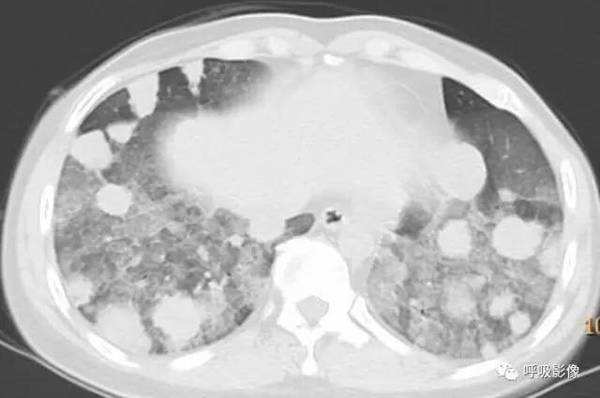

绒毛膜癌较侵袭性葡萄胎易发生转移。侵袭性葡萄胎肺部转移多以结节为主(图1),而绒毛膜癌肺部转移种类较多。

图1 女,31岁,侵袭性葡萄胎

转移灶的影像早期 可表现为不规则的小片状影或磨玻璃样阴影,逐渐增密、增粗,形成边缘不光滑的结节或肿块影,可伴出血,此时边缘毛糙,周围出现晕征、铺路石征等(图2)。

图2 女,39岁 绒癌双肺转移伴肺内出血。可见肺内磨玻璃影典挤和铺路石征。